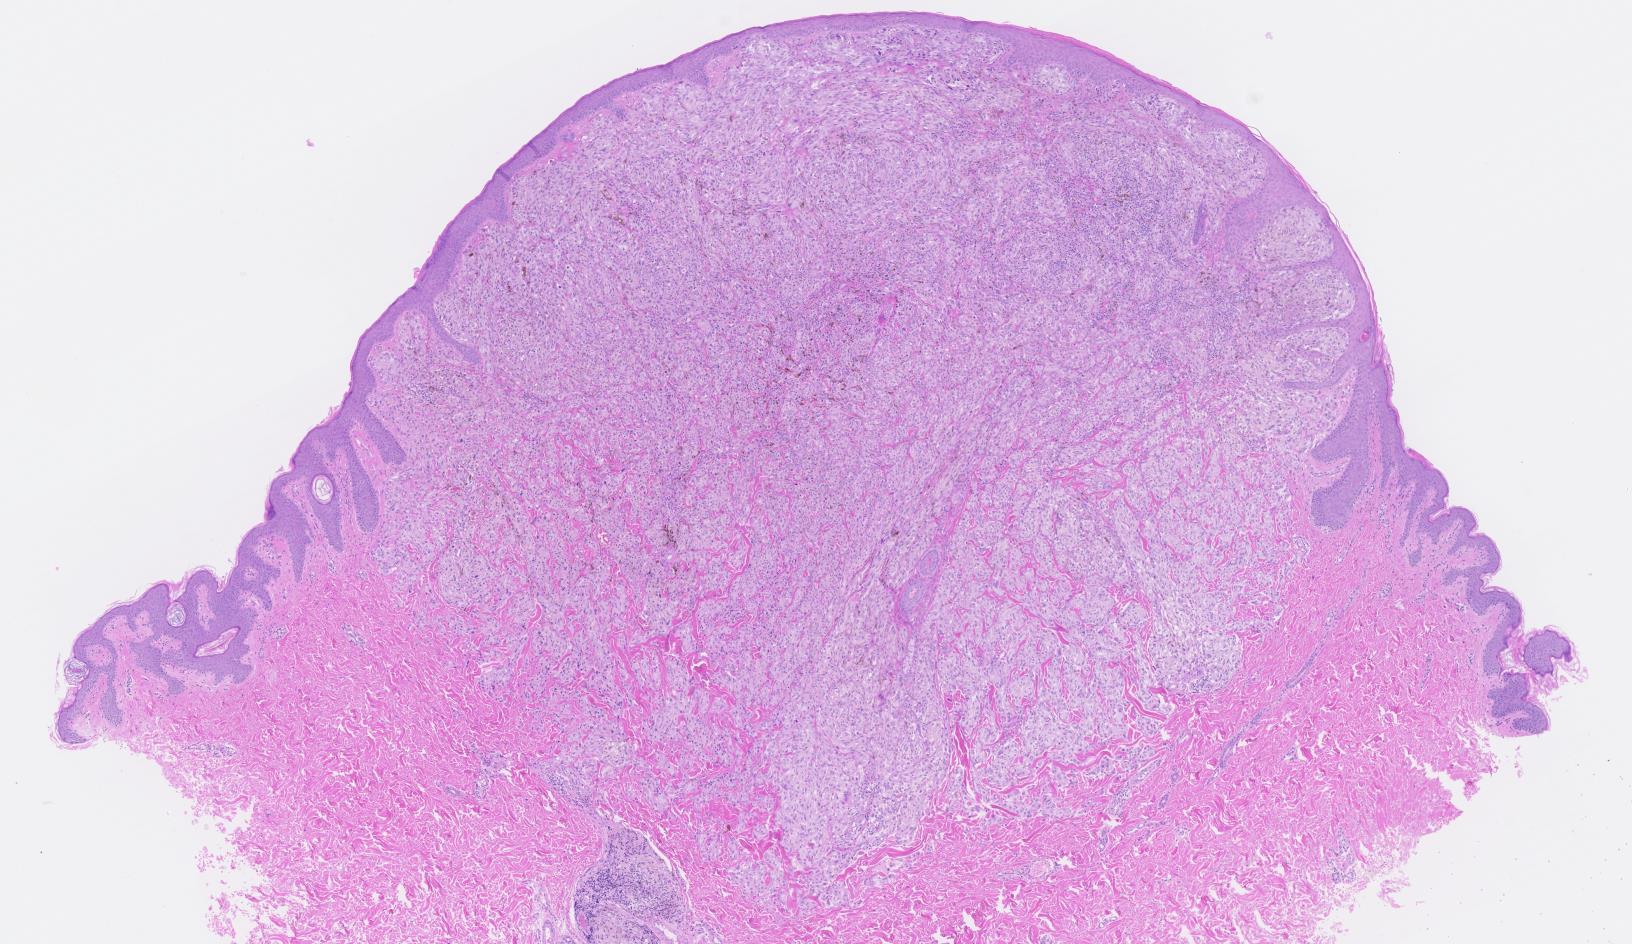

Nodular melanoma

• 2nd most common subtype of melanoma. It represents 15% of all melanomas.

• The most common sites for nodular melanoma are the trunk, head, and neck.

• Macroscopically, the lesion presents as a nodular, polypoid or pedunculated dark brown or blue black lesion. May also present as an amelanotic nodule.

• Often ulcerated

• Often no junctional component – dd. metastasis